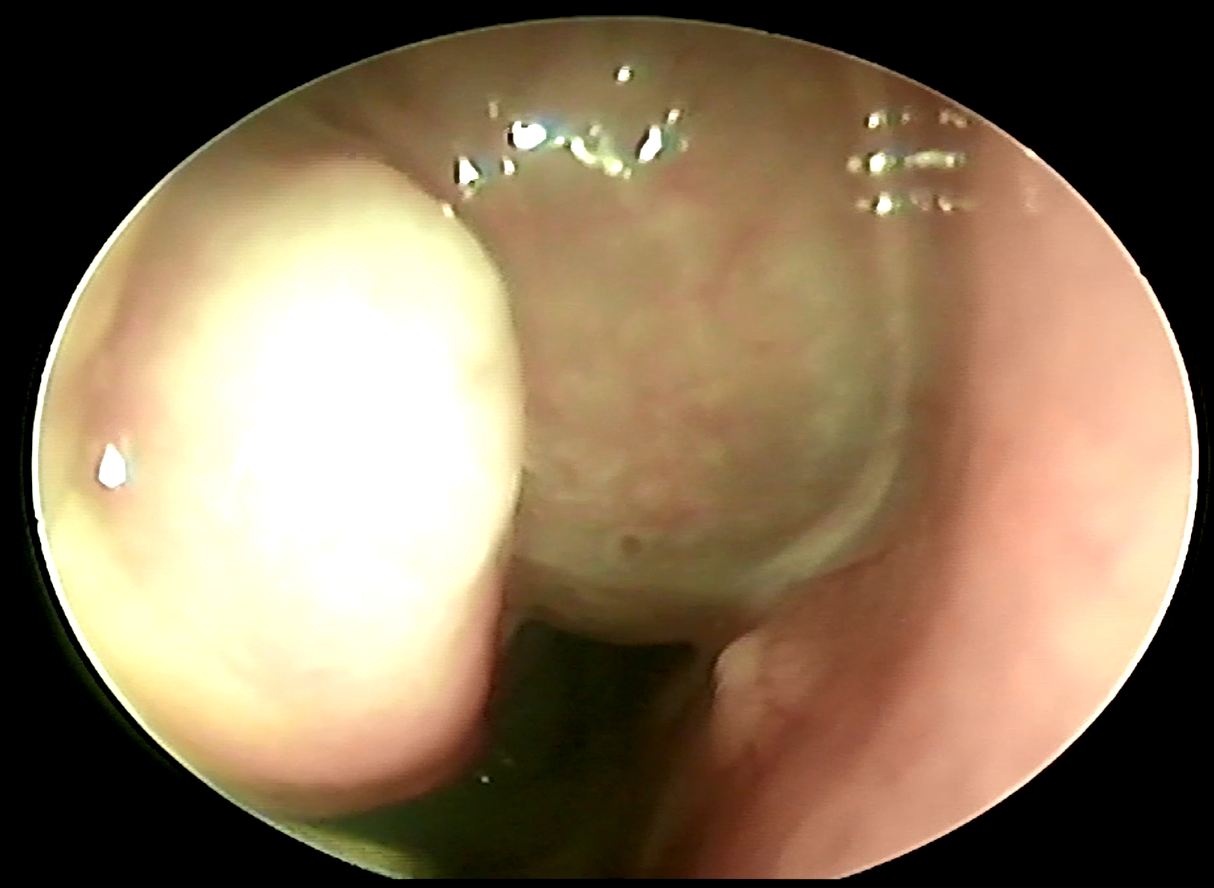

鼻竇是我們顱骨內的空腔,一般人通常會具有上頷竇、前篩竇、後篩竇、蝶竇、額竇等等,他們都跟我們的鼻腔有相通,所以通常鼻竇發炎的時候裡面的分泌物會跑到鼻腔中,導致病人會有膿鼻涕或是鼻涕倒流的症狀,一般來說鼻竇炎可以分為急性、亞急性或慢性,根據不同的感染原又可以分為細菌、病毒或是黴菌,其中最常見的是病毒性感染,每年在美國大約有3100人有得過鼻竇炎,是排名前五大可能會用到抗生素的疾病,當感染的時候鼻竇黏膜會腫脹導致鼻竇開口堵塞,同時病毒或細菌也會影響纖毛運動導致黏液排出困難進而堆積,所以就形成了更容易讓細菌或是病毒滋長的環境,一般來說超過10天以上都沒有任何進步的會高度懷疑是細菌性感染,或是一開始有進步又變嚴重了也會懷疑是細菌性感染,病毒感染通常是症狀治療,細菌性感染一般會給予抗生素,有時也會建議鼻內類固醇的使用以及鼻腔沖洗;一般鼻竇炎的診斷是依據病史以及理學檢查或室內視鏡檢查,不會常規使用影像學檢查除非是懷疑有併發症或是預計要手術治療的時候才會使用,影像學檢查無法判斷是細菌或是病毒性來源,至於細菌培養比較常用於懷疑有抗藥性的病人或是免疫不全的病人身上。

通常單側的鼻竇炎要最為小心,可能是腫瘤、黴菌感染或是牙科處置不當從口腔跑來的細菌,這時候藥物的治療反應就會不好,有時候甚至需要手術治療,鼻竇炎如果延遲治療有時候甚至會引起眼球或眼球旁膿瘍、腦部海綿竇栓塞、腦部膿瘍等等嚴重的併發症,所以如果一直有膿鼻涕沒有改善,請一定要給耳鼻喉專科醫師詳細檢查喔!!